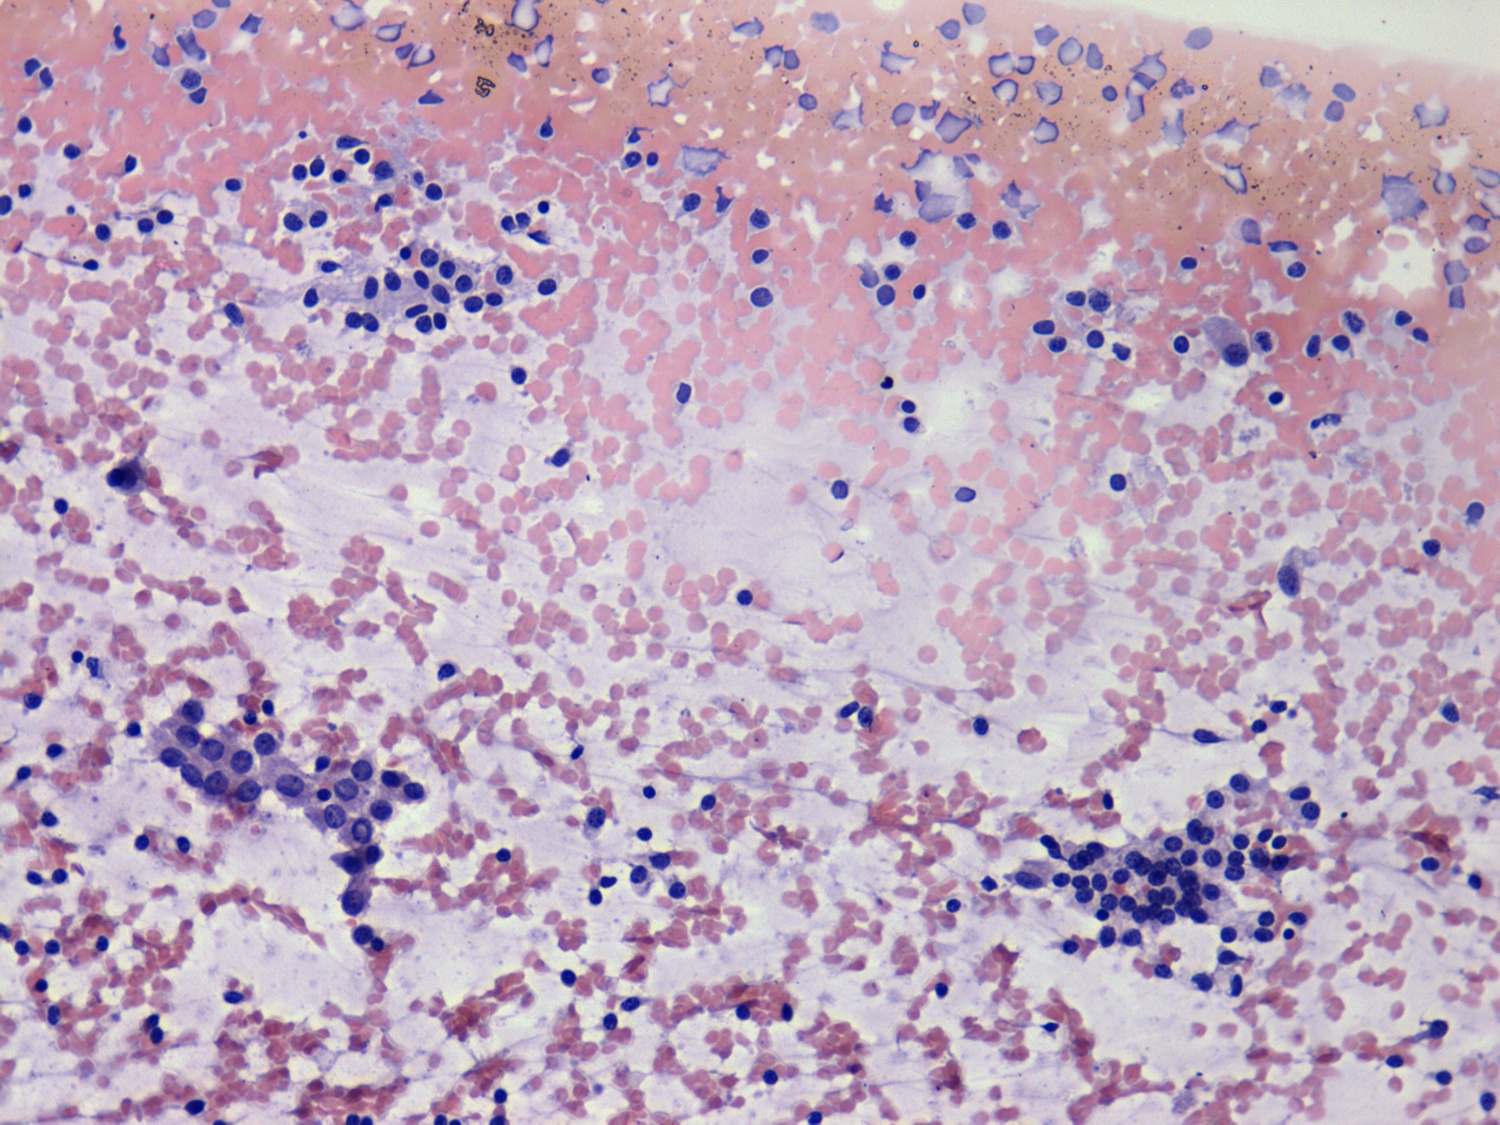

100 consecutive cases of papillary cancer - case 037 (cytologic picture 2)

Pap-smear, 200x. Note the difference between the two cell groups. The nuclei in the left cluster are larger and their chromatin structure is looser compared with the cell group in the right. There is an intranuclear inclusion in the former.